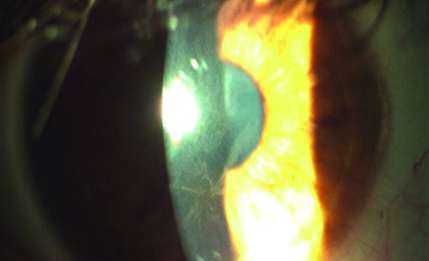

Oncologia oculare pediatrica: approccio clinico, ecografico e diagnosi differenziale in un...

L'oncologia oculare pediatrica rappresenta una sfida diagnostica per l’oftalmologo e il pediatra. Questo articolo descrive un caso...